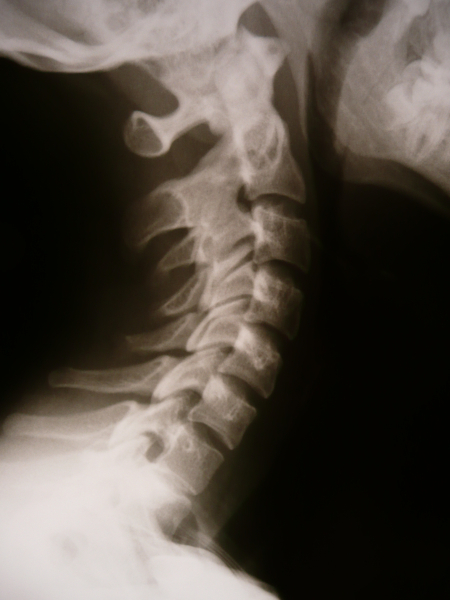

Диагностика синостоза включает в себя несколько этапов, начиная с осмотра врача и заканчивая инструментальными исследованиями. Во время осмотра врач обращает внимание на внешний вид и форму головы ребенка, а также на наличие асимметрии лица, глаз и ушей. Он также оценивает движение шейного позвонка и пытается определить наличие естественных швов и швов, которые могут быть покрыты коростой.

- Рентгеновское исследование головы и черепа. Рентгеновский метод может использоваться для оценки костей головы, включая швы и швы. Однако это исследование может быть менее информативным в сравнении с КТ и МРТ.